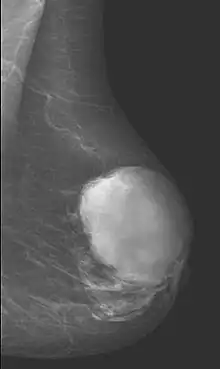

Radiographical imaging is the first-line test for identifying a phyllodes tumor.[11] Despite their propensity to grow rapidly and deform the overlying breast tissue, approximately 20% of phyllodes tumors can present as a nonpalpable mass on screening mammography.[12] Other imaging tools used to assess the size and spread of a phyllodes tumor include ultrasound and magnetic resonance imaging (MRI).[11] None of these imaging tools are definitive tests for differentiating a phyllodes tumor from a benign fibroadenoma.[13] Phyllodes tumors can only be diagnosed histologically, as they tend to have many overlapping features with other breast masses on physical examination and radiological imaging.[11]

.jpg)